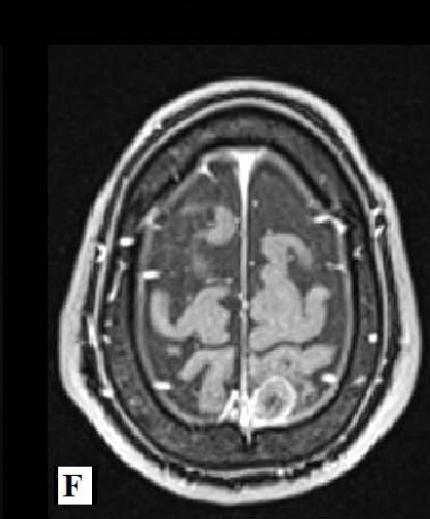

We report a rare case of Wilson’s Disease with neurologic features in a 31-year-old man. This disease consists of a disturbance of copper metabolism secondary to a mutation in the gene responsible for encoding the tissue transporter and the enzyme that incorporates the excess element into bile, generating toxic accumulation in the liver, cornea, and central nervous system. According to his wife, the patient had been treated for an unspecified mood disorder. The clinical picture was characterized by depressive mood, anhedonia, and anxiety. He had his first seizure episode on December 3rd, 2021. He progressed with dysarthria, ataxic gait, dystonia of the right-hand flexor muscles, and intermittent urinary incontinence. Marked worsening was observed after the diagnosis of COVID-19 in February 2022. At the clinical evaluation on March 24th, risorius muscle dystonia (risus sardonicus), resting tremor, and Kayser Fleischer rings at slit-lamp examination was also noted.